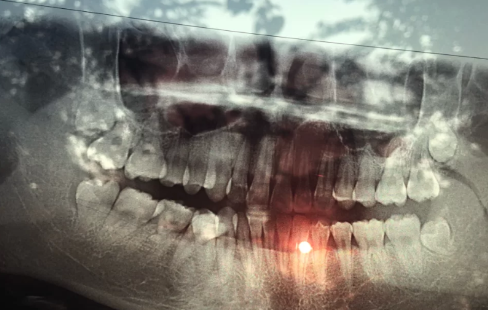

智齒是一種特殊的牙齒,牙根深而復(fù)雜,拔起來非常復(fù)雜。很多人不了解智齒,聽說智齒的全稱是智齒,以為智齒是智慧的象征,其實智齒跟沒有智慧的時候沒有半毛錢關(guān)系。有智齒的人不代表智慧高,沒有智齒的人也不代表智慧低。

智齒是口腔中牙槽骨最里面的第三顆臼齒,長得相對較晚,通常在16歲至25歲之間。個體之間智齒的生長有很大的差異。正常情況下,有4顆牙齒上下對稱,但有的人牙齒少于4顆或沒有牙齒,有的人一輩子都長不長,這是正常的生理現(xiàn)象。

由于智齒生長的位置特殊,很難清理干凈。如果口腔保健工作沒有做好,很容易發(fā)生智齒炎癥,可能需要考慮以拔牙的方式進(jìn)行治療。